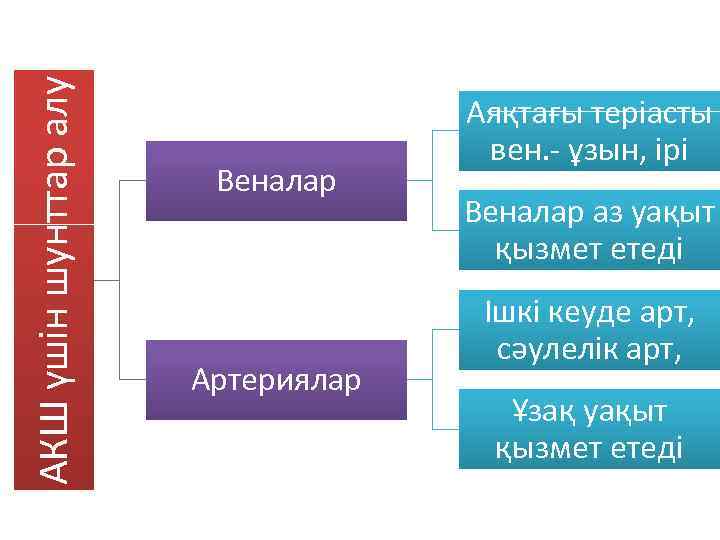

АКШ үшін шунттар алу Веналар Артериялар Аяқтағы теріасты вен. - ұзын, ірі Веналар аз уақыт қызмет етеді Ішкі кеуде арт, сәулелік арт, Ұзақ уақыт қызмет етеді

АКШ үшін шунттар алу Веналар Артериялар Аяқтағы теріасты вен. - ұзын, ірі Веналар аз уақыт қызмет етеді Ішкі кеуде арт, сәулелік арт, Ұзақ уақыт қызмет етеді